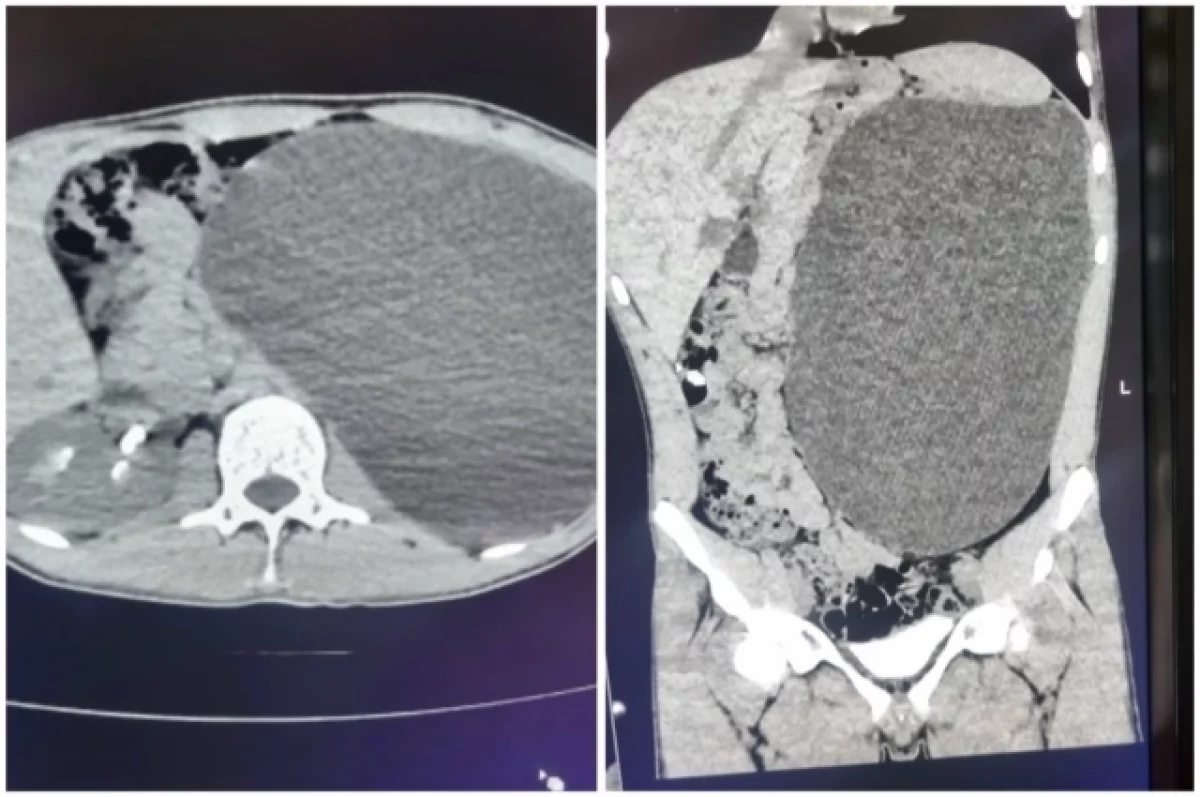

О болезни Михаил (имя изменено) узнал совершенно случайно. Он не испытывал никаких неприятных симптомов или недомогания, просто жил, планировал устроиться на работу, и для этого записался на профосмотр. Но приступить к трудовой деятельности не получилось. Сразу после УЗИ парня направили в стационар детской городской клинической больницы № 1. Снимок показал: левая почка настолько огромная, что её невозможно измерить специальным прибором.

Мальчик попал к детскому хирургу-урологу Ирине Живолуп. Медик быстро выявила гидронефроз. Это заболевание, при котором расширяется полостная система почки из-за нарушения оттока мочи. Что в свою очередь приводит к увеличению размеров почки, снижению её функции и риску развития серьёзных осложнений.

К сожалению, болезнь может долгое время протекать бессимптомно, как это и было у этого пациента. Но на профосмотре быстро нашли подозрительную аномалию. Юноше сразу провели операцию по удалению воспалённой почки, пока эта патология не привела к тяжёлым последствиям. Через небольшие проколы орган и скопившуюся жидкость вывели из брюшной полости.

«В данном случае существовал риск разрыва полостной системы почки, развития перитонита и внутрибрюшного кровотечения. Соответственно, исход непредсказуем», — ответила Ирина Живолуп.